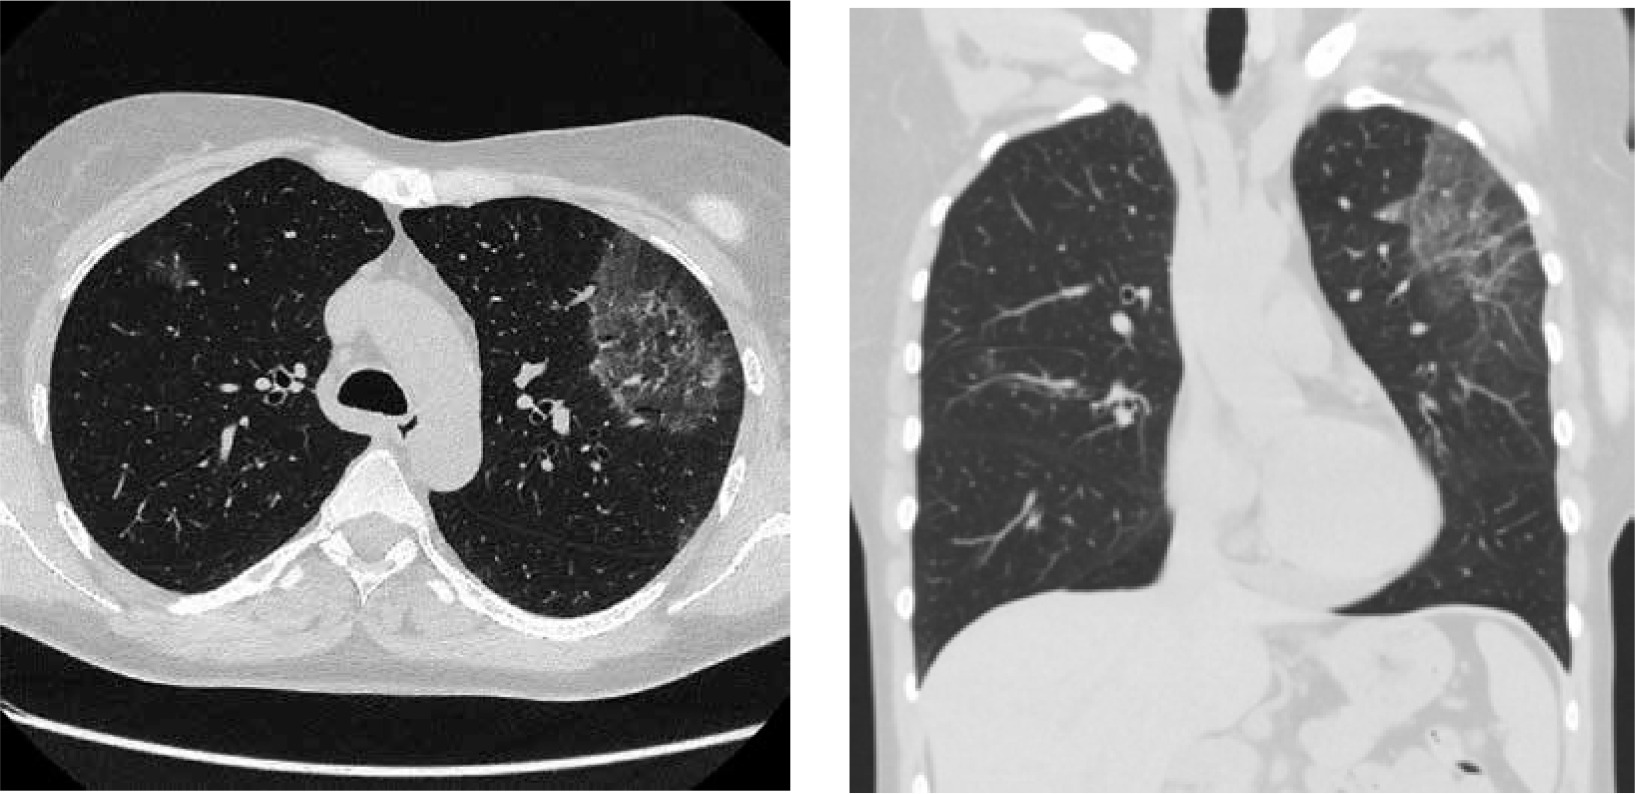

In December 2019 the patient was admitted to the Department of Rheumatology and Immunology due to exertional dyspnea and cough. Physical examination revealed diffuse expiratory wheezing and prolonged expiration. Initial workup revealed blood eosinophilia (2840 cells/µl) and an elevated level of immunoglobulin E (134 IU/ml, reference range < 100); with normal levels of vitamin B12, tryptase and immunoglobulin G. There were no parasitic eggs or larvae in a stool sample. The patient was negative for FIP1L1-PDGFRA, JAK2 and ETV6-PDGFRB mutations. A bone marrow aspirate revealed an elevated level of eosinophils (< 10% of the cells); no other pathologies were identified. Cytogenetic analysis showed a normal female karyotype. Ground glass opacities on high-resolution CT were described (Fig. 2). Bacterial and fungal cultures of BAL fluid did not yield any organisms. Increased eosinophils in BAL fluid (10%) confirmed HES flare. Therapy with intravenous methylprednisolone (40 mg daily for 5 days, subsequently tapered), combined with inhaled GC and bronchodilators was started. Reduction of methylprednisolone dose less than 32 mg daily led to HES flare.